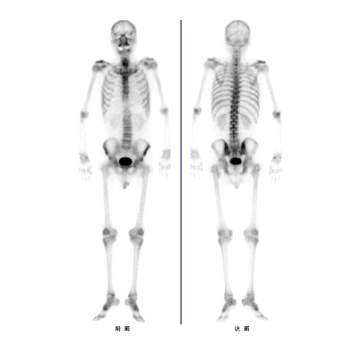

RI画像

骨シンチ